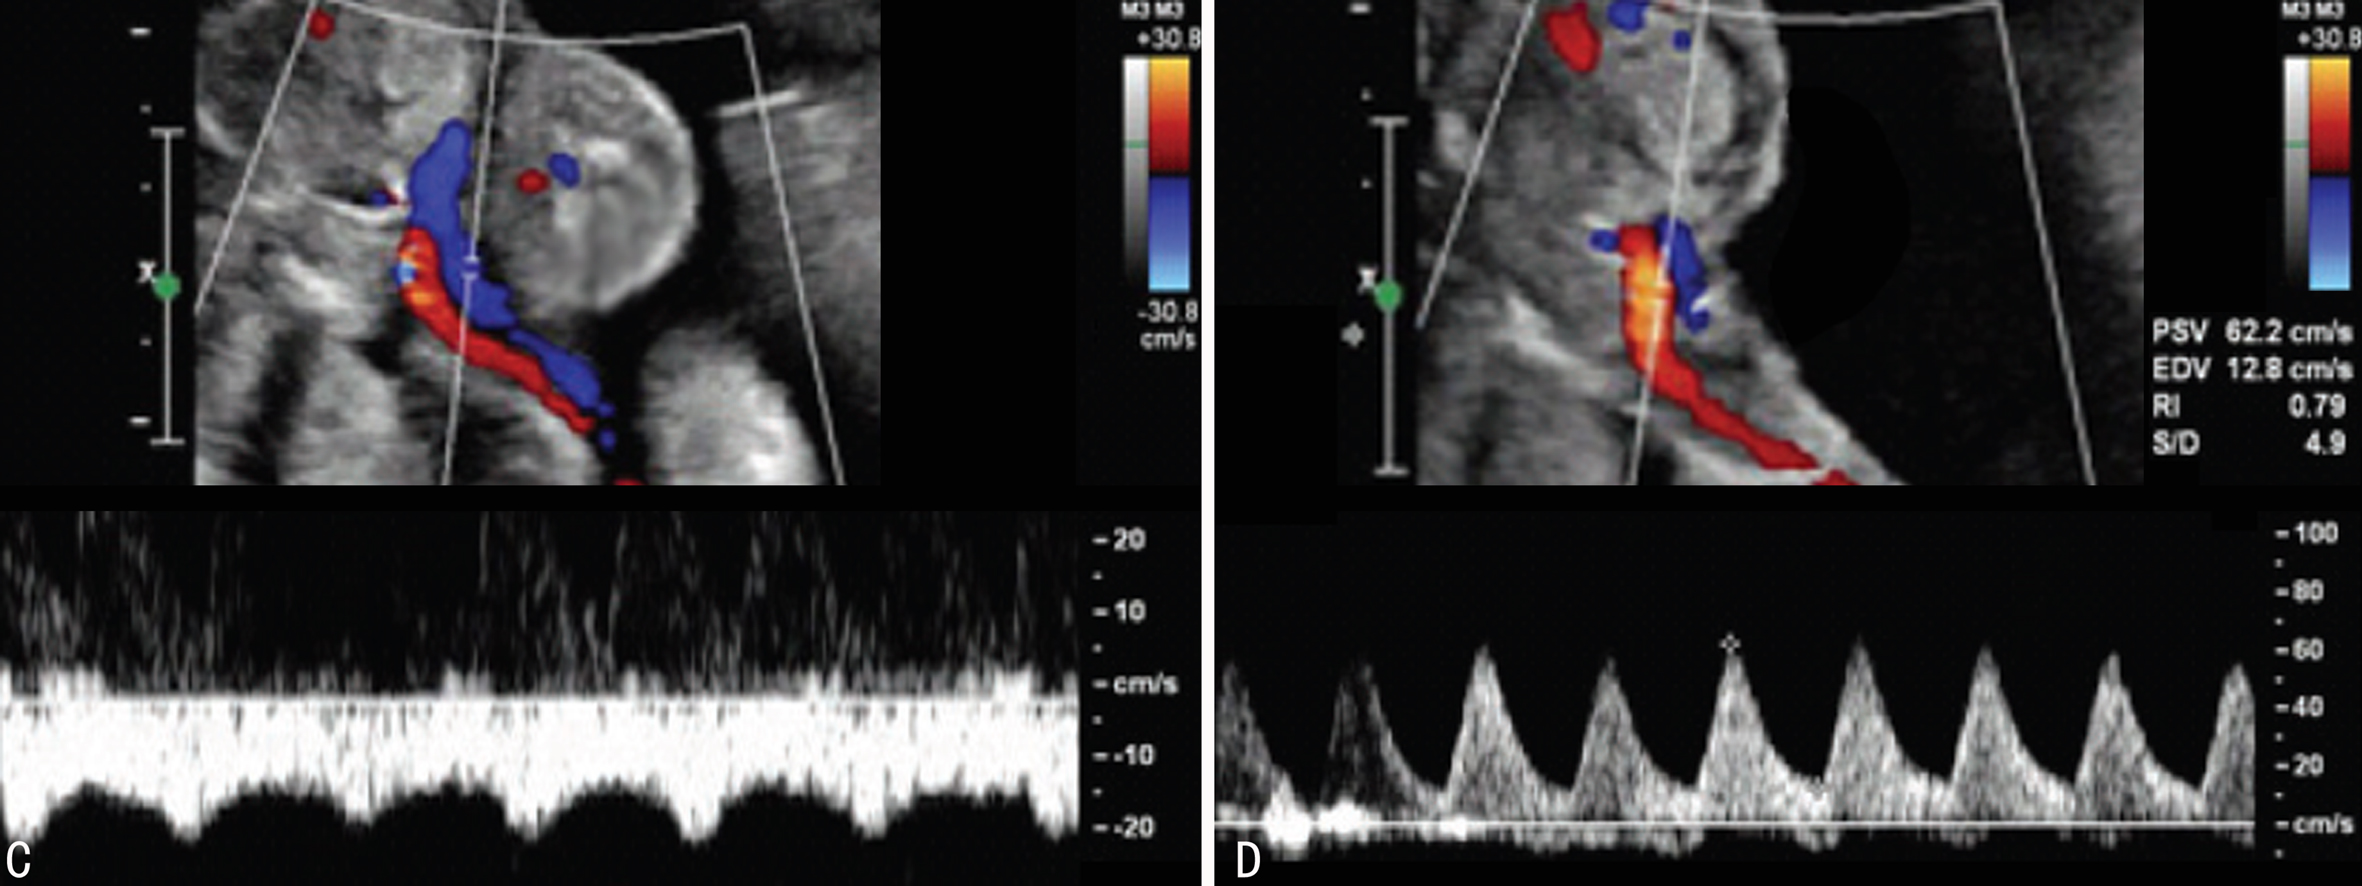

图3双胎动脉反流灌注序列超声检查

C:TRAP胎块脐动脉显示低阻力波动性频谱 D:TRAP胎块脐静脉显示高阻力波动性频谱